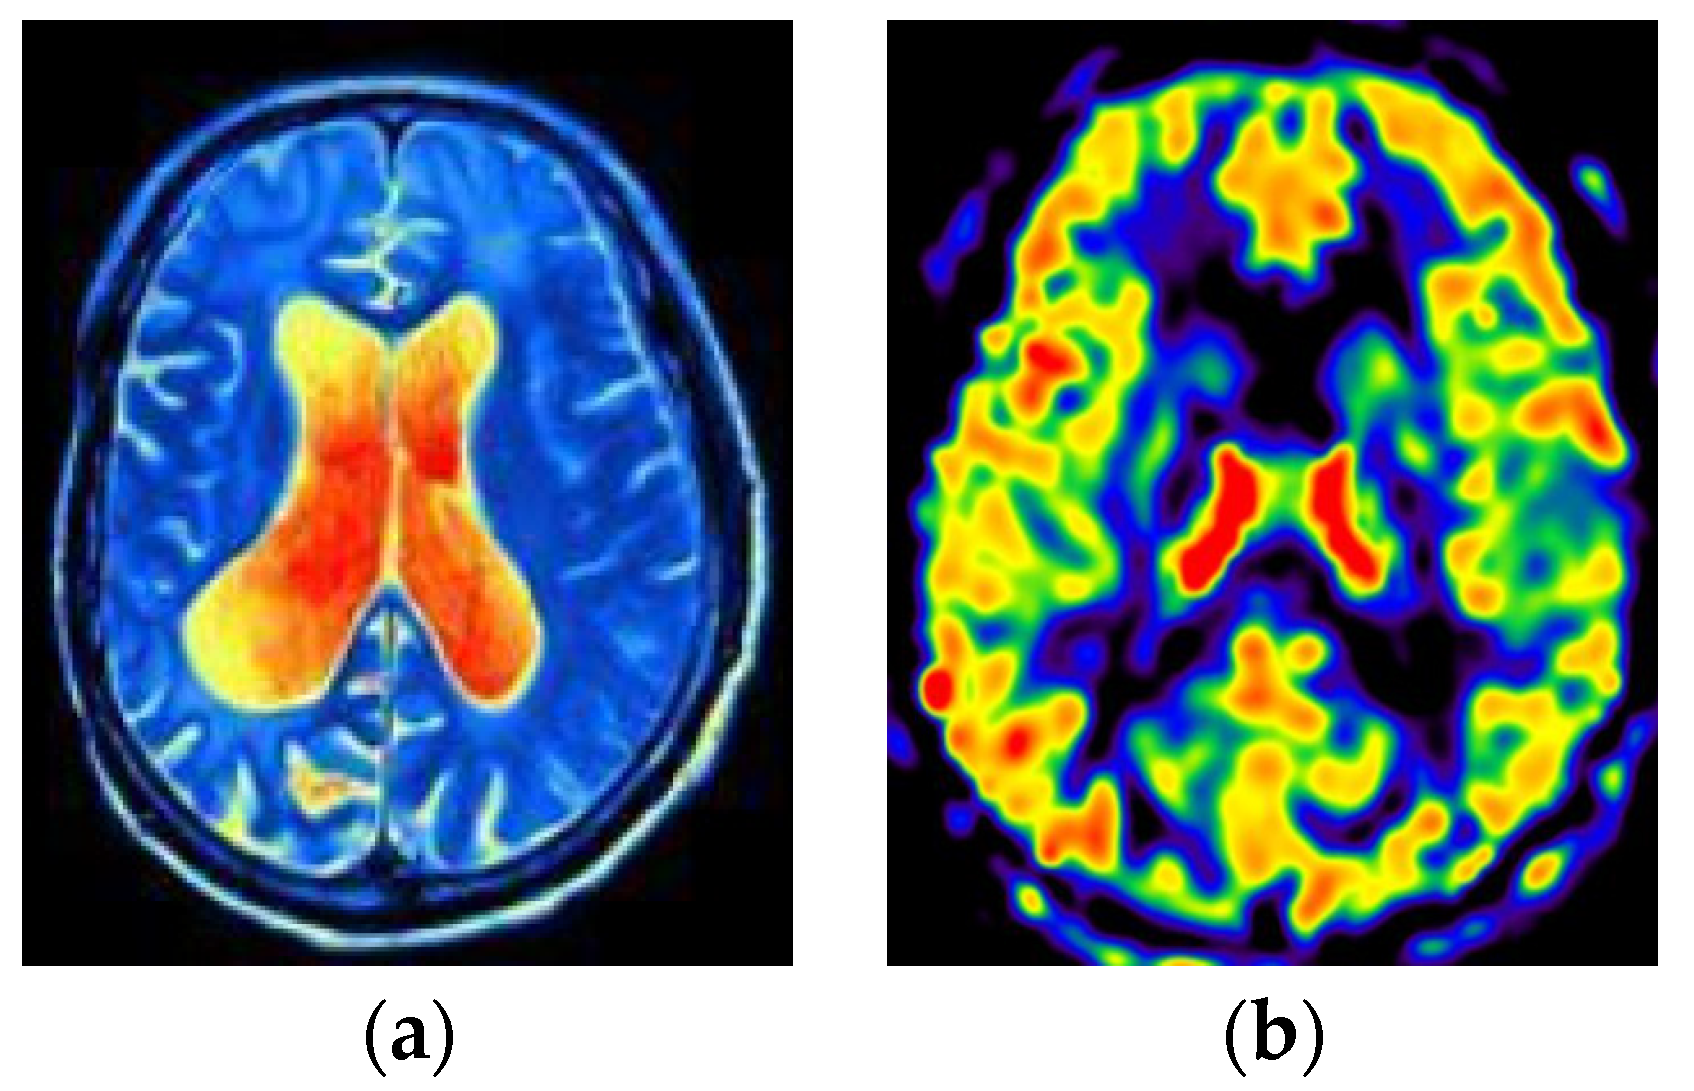

3.4. Data Visualization and Analysis